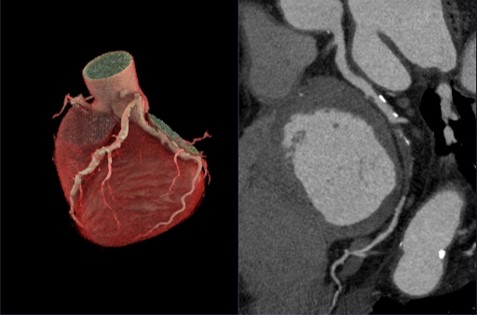

Maxima_Obayama02.jpg

図2. CT本体での解析画像 (HR76bpm)

CardIQ Xpress

Revolution Maximaでは、GEヘルスケア社製ワークステーションであるAdvantage Workstation(AW)に搭載される心臓解析アプリケーションであるCardIQ Xpressが搭載可能であり、撮影から解析までCT装置のみで完結可能である。

CardIQ Xpressでは冠動脈の自動抽出が行われ各冠動脈のCPR画像、Lumen画像、心臓3D画像、冠動脈MIP画像の作成が可能となっている。64列CT装置での心臓解析において血管ズレ(以下、バンディングアーチファクト)が問題となる事があるが、CardIQ Xpressにはバンディングアーチファクト補正機能であるIBR(図3)が搭載されており、高精度な血管認識によって血管走行をトラッキングし、解剖学的情報を基にバンディングアーチファクトを軽減した画像解析、画像出力が可能である。